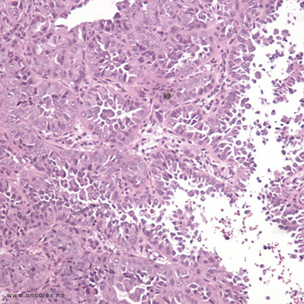

Bildeeksempler

Analyse av vevsprøver

Vevsprøver sendes til histologisk analyse. Analysene kan være avgjørende for hvilken behandling pasienten får.

Type 1: Den vanligste typen kreft i livmor utgår fra livmorslimhinnen og kalles endometrioidadenokarsinom. Dette betegnes som type 1. Denne svulsttypen forekommer som regel hos kvinner i eller rundt den reproduktive overgangsalderen. Den påvirkes av hormonnivåer, særlig østrogen. Type 1-svulster har generelt en god prognose, men type 1/grad 3-svulster har en noe dårligere prognose enn type 2-svulster.

Type 2: Svulster av type 2 ses hos eldre kvinner (gjerne over 60 år) uten tegn på langvarig østrogenstimulering. De består i hovedsak av serøst papillært adenokarsinom og klarcellet adenokarsinom.

• Endometrioid adenokarsionom (75 %–80 %)

• Serøst papillært karsinom (< 10 %)

• Mucinøst (slimproduserende celler) karsinom (1 %)

• Klarcellet (klare/bleke celler) karsinom (4 %)